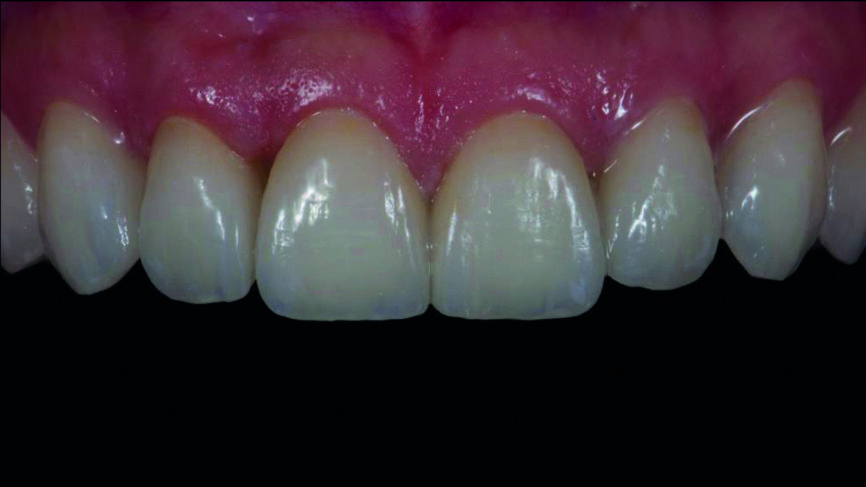

Fig. 17a : Résultat final une semaine plus tard.

Fig. 17b : Résultat final une semaine plus tard, vue de face

Le clinicien et la patiente ont décidé subjectivement un scellement des facettes en céramique feldspathique en raison des légères différences dans la longueur des incisives centrales des deux jeux. Les procédures adhésives ont suivi (Figs. 16a–f) et des photographies intra-orales et extraorales ont finalement été prises une semaine plus tard (Figs. 17a–e).